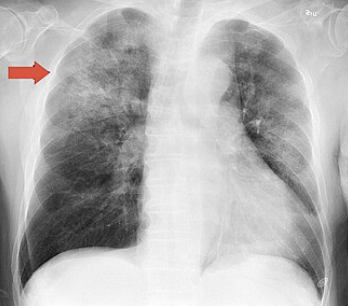

Haemophilus influenzae

• Chest radiograph and influenza and H. Influenza, posterioanterior, annotated JPEG